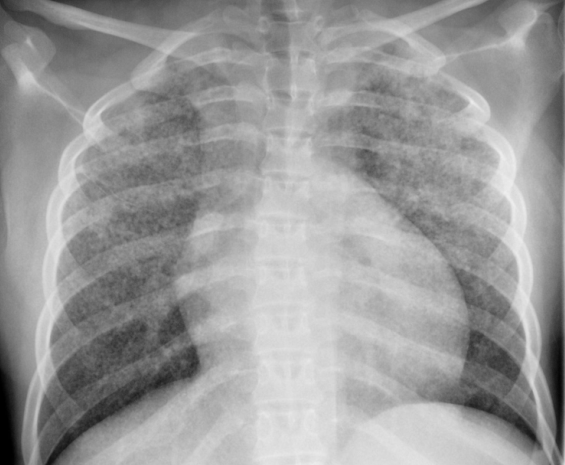

Viene dunque eseguita una radiografia del torace che mostra un quadro di infiltrazione micronodulare bilaterale diffusa (Figura 1) confermato anche alla TAC (Figura 2).

Figura 1. Diffusamente e bilateralmente sono presenti innumerevoli noduli millimetrici, ben definiti, di 1-4 mm di diametro, distribuiti prevalentemente nei campi polmonari superiori.